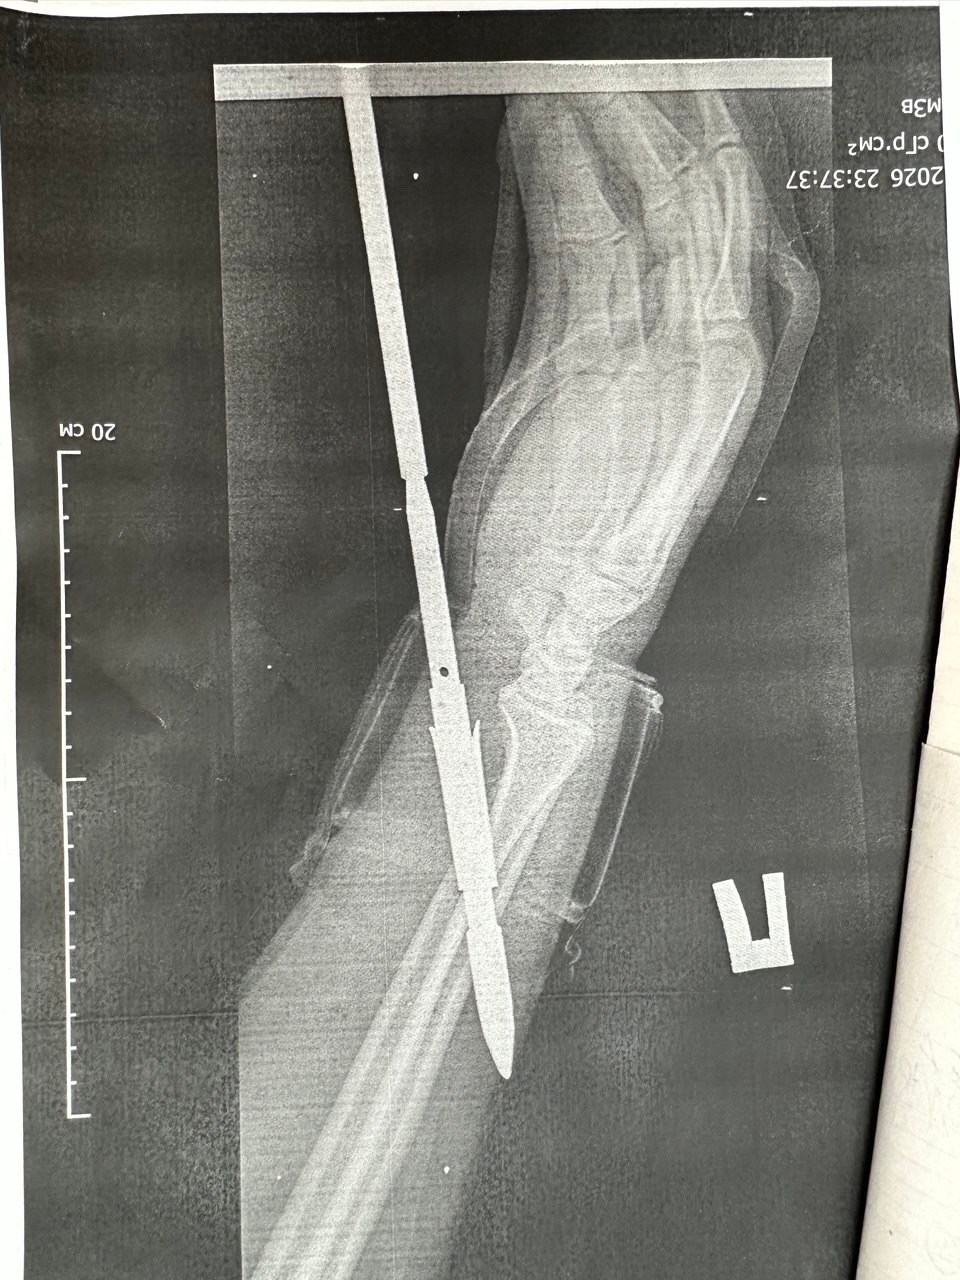

«Гарпун с двумя зубцами прошел между костями, не задев их. Специалисты извлекли инородное тело, обработали колотую рану и оказали пациенту квалифицированную помощь», — говорится в публикации.